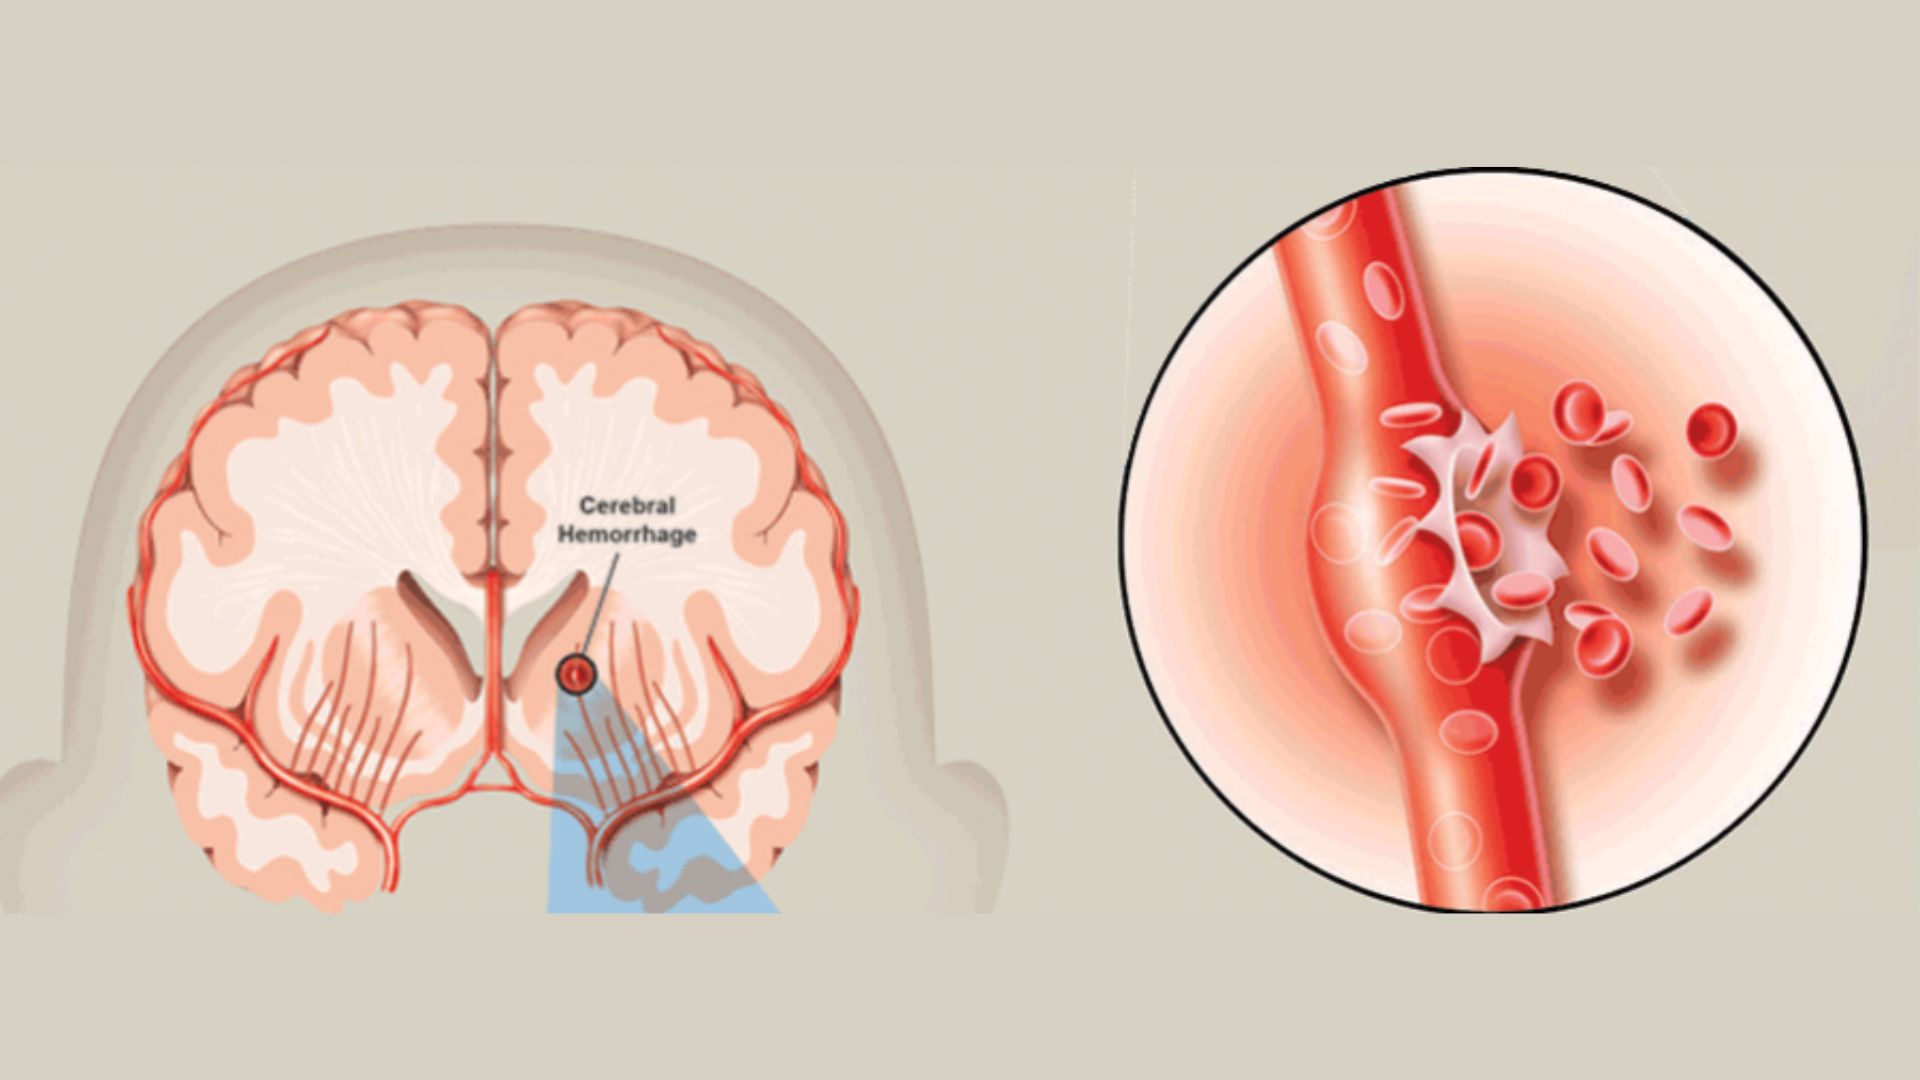

Hội chứng nhồi máu não lỗ khuyết (đột quỵ ổ khuyết) có thể để lại nhiều biến chứng nguy hiểm cho người bệnh, là nguyên nhân dẫn tới tử vong. Theo thống kê, có khoảng 25% các trường hợp đột quỵ nhồi máu não là nhồi máu não lỗ khuyết. Đây là một dạng của đột quỵ nhồi máu não, xảy ra khi các mạch máu nhỏ nằm sâu trong não bị tắc.

Nhồi máu não lỗ khuyết là những ổ tổn thương nhỏ dưới vỏ có đường kính dưới 15mm do tắc các tiểu động mạch hoặc động mạch xiên (penetrating arteries) là những nhánh tách trực tiếp từ các động mạch não lớn, thường gặp nhất là từ đa giác Willis, động mạch não giữa và động mạch nền.

Nhồi máu não lỗ khuyết xảy ra khi mạch máu cung cấp cho các cấu trúc sâu bên dưới não đột ngột bị tắc, gây ra những tổn thương nhỏ trong não. Yếu tố nguy cơ quan trọng nhất là huyết áp cao mạn tính. Tình trạng này có thể khiến mạch máu bị thu hẹp. Từ đó, các mảng cholesterol hoặc cục máu đông dễ dàng gây tắc dòng máu đến các mô não sâu.